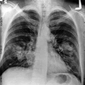

Temiz Akciğer Tomografisi Ne Anlama Geliyor?Günümüzde tıpta tanı ve tedavi süreçlerinde önemli bir yer tutan görüntüleme yöntemlerinden biri olan akciğer tomografisi, hastalıkların teşhisinde kritik bir rol oynamaktadır. "Temiz akciğer tomografisi" ifadesi, genellikle akciğerlerde herhangi bir anormal bulguya rastlanmadığı anlamına gelir. Bu bağlamda, temiz bir akciğer tomografisi sonucu, hastanın akciğer sağlığının iyi olduğunu gösterir. Akciğer Tomografisi Nedir?Akciğer tomografisi, yüksek çözünürlüklü görüntüler elde etmek için X-ray teknolojisini kullanan bir görüntüleme yöntemidir. Bu yöntem, akciğerlerin iç yapısının detaylı bir şekilde incelenmesine olanak tanır. Tomografi, akciğerlerdeki lezyonlar, tümörler, enfeksiyonlar ve diğer patolojilerin tespit edilmesinde son derece etkili bir yöntemdir. Temiz Akciğer Tomografisi SonucuTemiz bir akciğer tomografisi sonucu, şu durumları ifade edebilir:

Bu sonuç, genellikle hastanın akciğer sağlığının iyi olduğunu ve herhangi bir ciddi patoloji olmadığını gösterir. Ancak, bu sonuçlar her zaman kesin bir tanı anlamına gelmez; doktorun klinik değerlendirmesi ve hastanın genel sağlık durumu da göz önünde bulundurulmalıdır. Temiz Akciğer Tomografisinin ÖnemiTemiz akciğer tomografisi sonucu, özellikle kronik akciğer hastalığı, kanser riski veya enfeksiyon öyküsü bulunan hastalar için büyük bir rahatlık kaynağıdır. Bu durum, hastaların tedavi süreçlerine olumlu yönde katkı sağlar ve gereksiz endişeleri azaltır. Ayrıca, temiz bir tomografi sonucu, sağlık profesyonellerine hastanın durumu hakkında daha fazla bilgi verir ve gelecekteki muayene ve tedavi planlamalarına yardımcı olur. SonuçTemiz akciğer tomografisi, akciğer sağlığının iyi olduğunu gösteren önemli bir bulgudur. Ancak, bu sonucun değerlendirilmesi için mutlaka bir sağlık profesyoneliyle görüşülmesi gerektiği unutulmamalıdır. Her durumda, kişinin genel sağlık durumu, belirtiler ve diğer tetkiklerin sonuçları birlikte ele alınmalıdır. Sağlıklı bir yaşam tarzı, düzenli kontroller ve zamanında yapılan tetkikler, akciğer sağlığının korunmasında önemli rol oynamaktadır. |